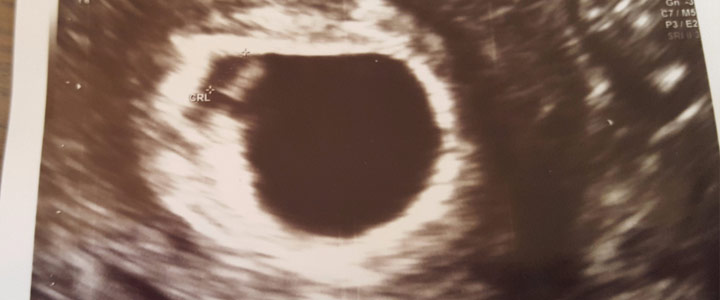

Zal het hartje nog wel kloppen?

Klein vlekje knipperde op de echo Op de laatste echo zagen we een klein vlekje dat knipperde. Een vervolgafspraak gemaakt voor 2 weken later, dan kunnen we precies zien hoever ik ben. Helemaal gerustgesteld en in de ...